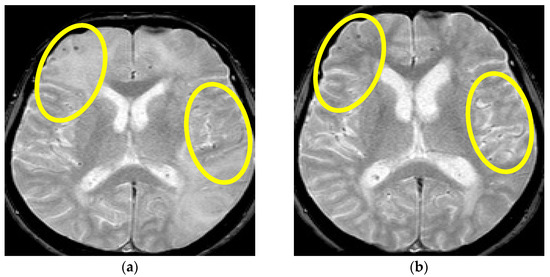

Figure 1.

Initial brain MR T2 sequence at admission and before therapy initiation (a) and one month after therapy initiation (b). Yellow arrows are showing confluent and extensive bilateral periventricular hyperintensities in (a) and reduction of hyperintensities of the same locations on (b). (Patient No. 1).

Since the patient fulfilled all the criteria for the diagnosis of probable CAA-ri (age > 40 years, decreased consciousness, with the presence of behavioral changes and focal neurologic deficit, MR signs of asymmetric WMH lesions and cerebral microbleeds, with the absence of other possible causes), the patient was initially treated with antihypertensive and anti-edematous therapy, together with IV dexamethasone (8 mg/daily) for 10 days, followed by pulse methylprednisolone therapy (1000 mg/day) for 5 days, after which oral prednisone (1 mg/kg) was slowly tapered down. The patient’s neurological status improved and he showed very discrete hemiparesis and normal gait, and the patient was alert and oriented. A neurological examination was almost without significant impairment and sequelae. A control CSF examination was performed, where normal levels of protein and glycose were detected. A normal cell count was present, and no OCB were registered. Control brain MR showed edema reduction with less extended WMH lesions (Figure 1 and Figure 2). The post treatment neuropsychological examination was without significant impairment.